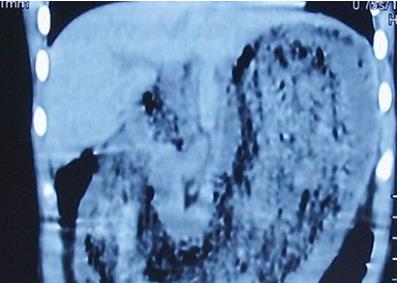

2/3胃被头发团占据了

一段时间以来,孩子总说胃疼、肚子疼,做什么好吃的也吃不下,几口就饱了。起初家长以为可能是天热,但孩子还是坚持说胃疼、肚子疼。带她去当地医院做检查,查血、做b超、做ct结果一切正常。但孩子还是坚称胃疼,饭菜仍然吃不下,转到市妇儿医院外科后,姜先敏建议做个胃镜看看。这一查,让医生们惊住了:“胃里有个‘大石头’,上面密密麻麻的全是头发。”“大石头”是头发和各种食物残渣长时间不断凝结形成的,占据了孩子2/3胃。

头发必须得取出来,如果再长时间不取,占据胃部空间,孩子仍然吃不下饭,从头发石头的大小看,根本不可能自动排出。更严重的是,再压在胃里一段时间,会有腐蚀,给胃造成溃疡乃至穿孔的风险。